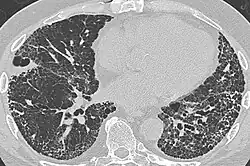

CT scan in a patient with usual interstitial pneumonia, showing interstitial thickening, architectural distortion, honeycombing and bronchiectasis.

In radiology, honeycombing or "honeycomb lung" is the radiological appearance seen with widespread pulmonary fibrosis[1] and is defined by the presence of small cystic spaces with irregularly thickened walls composed of fibrous tissue. Dilated and thickened terminal and respiratory bronchioles produce cystic airspaces, giving a honeycomb appearance on chest x-rays. Honeycomb cysts often predominate in the peripheral and pleural/subpleural lung regions regardless of their cause.

Subpleural honeycomb cysts typically occur in several contiguous layers. This finding can allow honeycombing to be distinguished from paraseptal emphysema in which subpleural cysts usually occur in a single layer.